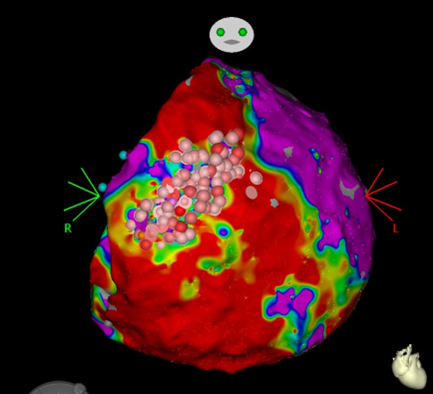

In our special consultation hours, we create a personal treatment strategy for each patient together with the resident doctors. After an initial attempt to control the rhythm with medication, and in some cases even before that, catheter ablation has established itself as the method of choice for treating atrial fibrillation. In the case of paroxysmal atrial fibrillation and the absence of structural heart disease, 70-90% of patients can be treated successfully. In patients with heart failure, it has even been shown that catheter ablation of atrial fibrillation can increase the probability of survival. Basically, the earlier the treatment, the higher the chances of success. Our center uses state-of-the-art methods using CT (Fig. 1) and MRI, fusion procedures with moving fluoroscopic images and 3D mapping systems.